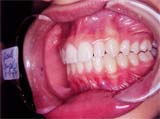

Vista lateral direita fig.11

Vista lateral esquerda fig. 12,

demonstrando que o lado onde foi trabalhado agora se apresenta igual ao lado normal do paciente, como nunca houvesse uma mordida cruzada do lado direito. Tempo de tratamento ativo – 5 meses.